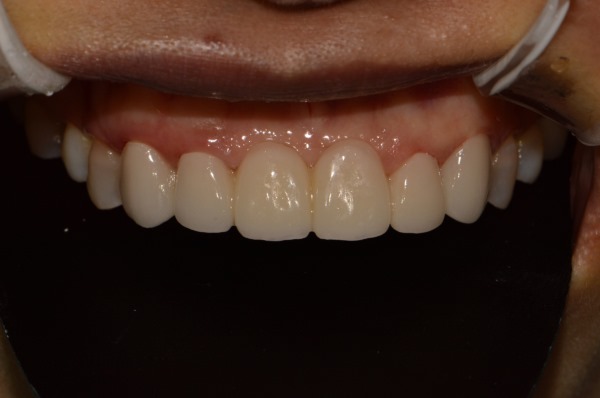

위 사진은 잇.몸.성.형 후 올세라믹 크라운 세팅하셨네요.

치아의 투명도, 크기 ,모양, 잇몸라인 꽤 괜찮아 보입니다. 환자분도 만족하셨고요.

잇몸라인의 확실한 변화 아래 사진처럼 잇몸라인의 굴곡은 어느 정도 확실하게 표현되어야 합니다. 통자 몸매가 예쁘지 않듯, 잇몸라인의 굴곡도 있어야 예쁘겠죠?